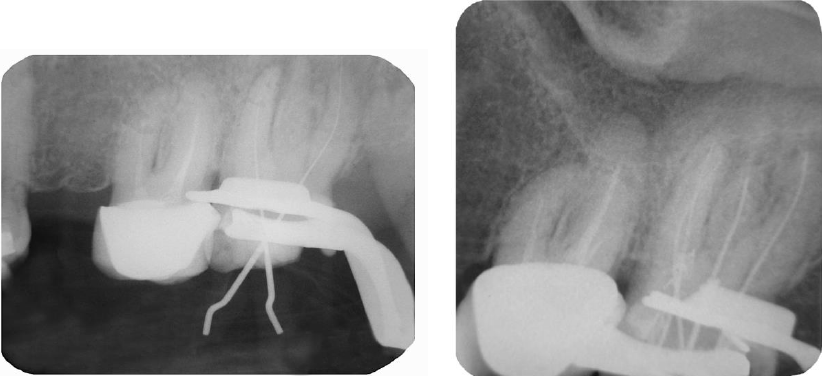

Se estableció la conductometría real de los cuatro conductos usando el localizador electrónico de forámenes apicales Root Zx II J. Morita. (MFG Corp, Japan) así como la verificación radiográfica. (Fig. 3 A, B) En este punto podemos clasificar el diente con dos conductos vestubulares uno MV y DV y dos conductos palatinos MP y DP.